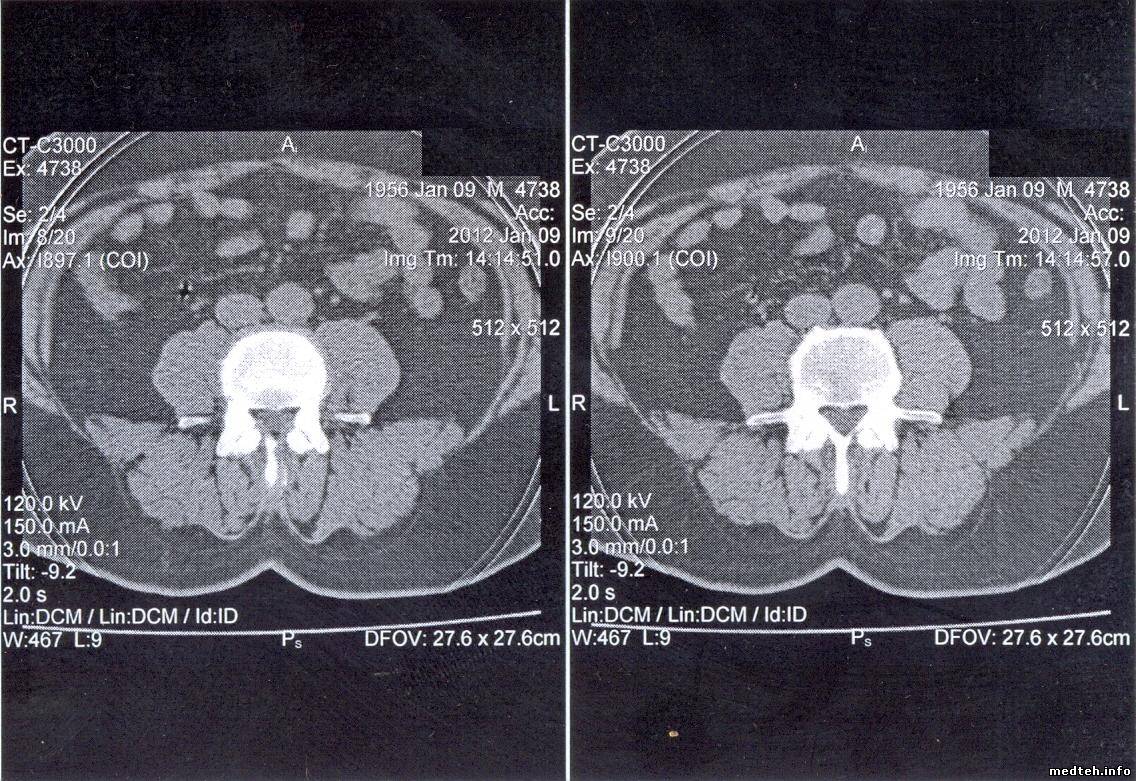

1. Черные точки в лобной доле правого полушария. Врачи говорят, что появляются внесистемно и они их путают с зоной ишемического инсульта. При повторных исследованиях головного мозга этого же пациента такой проблемы не обнаруживается. Говорят, что это связано с температурой. Как объяснить это, мне не очень понятно.

3. Кольцевые круги. Врачи говорят, что зависит от температуры в помещении, где установлен томограф (там стоит мощная сплит-система), При 25 есть, при 21 градусе исчезает. По словам врачей, лечилось это раньше калибровкой по фантому. Пока ее не делал. Не совсем понимаю, как это связано с температурой.